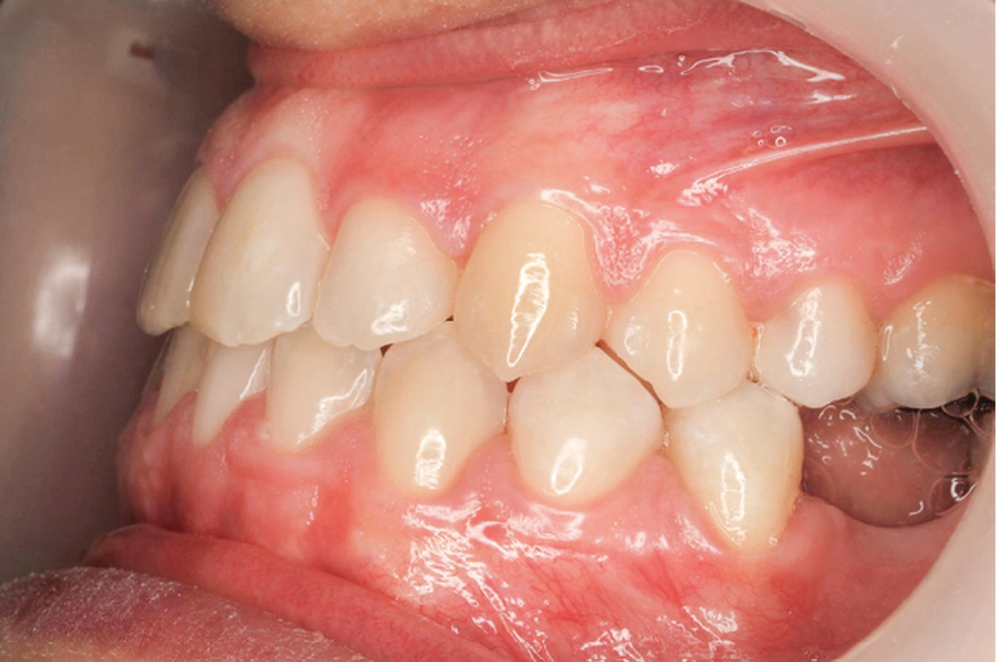

- Septième rendez-vous : les appareils sont déposés. Une empreinte numérique est prise pour réaliser trois aligneurs afin de parfaire le résultat occlusal et esthétique (fig. 3a-h).

L’outil 3D nous permet de contrôler et maîtriser la conception/fabrication des appareils linguaux et des aligneurs, combinant et optimisant ainsi avantageusement les qualités des deux appareils.

Finalement, les aligneurs permettent les ajustements occlusaux fins et précis de finition.